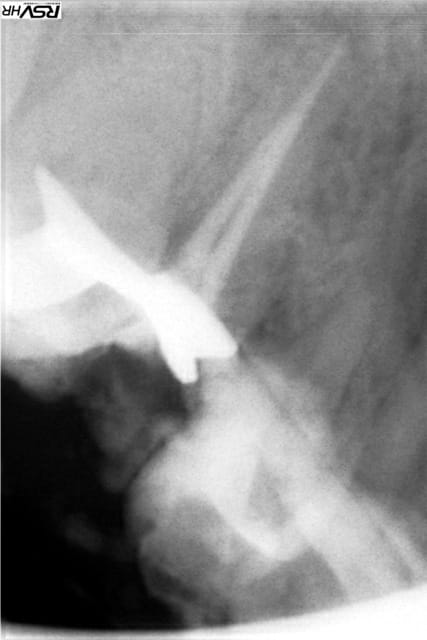

un post pour montrer que :reprise de traitement canalaire

sous digue+hypo+gutta compactée mac spaden peut fonctionner

RTE en 2013 ;guérison en 2015